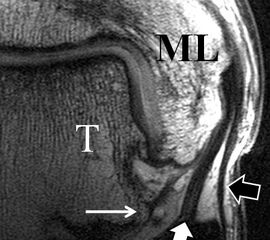

Jedoch findet man sich auch hier mit dem Problem der in den Standard-Projektionen schräg verlaufenden Syndesmose konfrontiert. Der oligofaszikuläre Aspekt der vorderen Syndesmose kann in der axialen Schnittebene eine zum Verwechseln ähnliche Morphologie wie eine Ruptur aufweisen (Abb. 15 b und c). Doppelangulierte Schnitte entlang der Achse (schräg koronar/schräg sagittal) lassen hingegen eine eindeutige Beurteilung der Bandstrukturen zu (Abb. 16) und verbessern die Syndesmosendiagnostik.

Bezogen auf die Transversalebene verläuft die Syndesmose ca. 30° schräg cranio-caudal anguliert (Abb. 15 a). Häufig lassen sich drei Hauptfaszikel differenzieren: das kürzeste superiore, das stärkste mittlere und das längste kaudale Faserbündel. Ein akzessorisches Bündel, das anteriore-inferiore, tibiofibulare Ligament (AITFL) oder auch Bassett-Ligament wird in 80-94% der Patienten nachgewiesen 8. Dies weist einen unmittelbaren Bezug zur anterolateralen Talusschulter auf (Abb. 17). In Kombination mit einer Außenbandinstabilität und konsekutivem, talarem Vorschub kann dieses zu einem Impingement an der anterolateralen Taluskante führen mit nachfolgender chondraler oder osteochondraler Läsion.